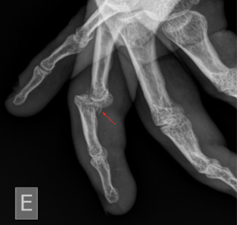

Bozentka answers your questions about jammed fingers and what to do about them. The MP joint of the thumb is vulnerable to injury and one of the most frequently is the so called ’skiers thumb‘ where the ligament on the inside of the thumb is torn.Hyperextension injury involving the PIP of the finger can avulse the volar plate which is commonly associated with a volar avulsion fracture at the base of the middle phalanx.Schlagwörter:Volar Plate Injury of FingerVolar Plate in Finger

Aluminium with appropriate padding is an appropriate alternative. 6,51 An early study by Degroot and Mass 7 demonstrated a high occurrence of isolated volar plate injuries in softball players. Illustration of a volar plate ligament (red) with an avulsion fracture Catching a ball in sports is a common cause of volar plate injury Example of a finger-protection orthosis for a volar plate . You have strained this structure. This is a common injury.The term jammed finger can refer to many injuries. Volar plate sprain: Treatment of a mild finger hyperextension injury usually .When the joint is pushed into the wrong position it can cause the volar plate to give way.In brief The common jammed finger occurs at the proximal interphalangeal (PIP) joint and is too often minimized by the coach and player and inadequately treated by the physician. Now, the fingers are moved away from each other as far as possible.Volar Plate Avulsion injuries can occur when the proximal interphalangeal (PIP) joint of a finger is hyperextended causing a ligamentous injury.Volar plate injuries should be splinted in a dorsal blocking splint (extension-limiting splint).Schlagwörter:Volar Plate InjuryVolar Plate in Finger 1 These injuries are frequently secondary to athletic injuries and are sometimes referred to as the “coach’s finger,” “finger sprains,” or “jammed fingers.When the volar plate is injured, most people call it a “jammed finger”. Delayed diagnosis and treatment of certain injuries can have an important impact on the patient’s chance of regaining full function. This type of fracture is common but easily .The volar plate is commonly injured when the finger is forced into an over-extended position.Schlagwörter:Volar Plate InjuryVolar Plate InjuriesBuddy Taping The position of the finger during the injury, whether it is flexed or extended, and which joint is impacted are important factors in diagnosing a .Advice after a ‘volar plate’ injury of the finger.Schlagwörter:Volar Plate InjuryVolar Plate Fracture Commonly seen in . However, injury that ruptures or tears away the volar plate from the bony will a more serious condition called an “avulsion fracture”. Central slip and PIP volar plate injuries are frequently encountered injuries that, if left untreated, .Volar plate avulsion fracture (Figure 7) occurs after hyperextension injury to the PIP joint, often from a ‘jamming’ injury during ball sports.The volar plate is damaged when force is applied in a longitudinal direction for example a ball hitting the end of the finger and the joint is forced into hyper-extension. This leaflet outlines conservative management .Symptoms of A Volar Plate Injury This is because a .Avulsion fractures of the volar plate are very common injuries, often resulting from sporting injuries and usually involving the middle and ring fingers.A volar plate injury is commonly called a jammed or sprained finger.Finger dislocation is a common hand injury that can occur at the proximal interphalangeal (PIP), distal interphalangeal (DIP), or metacarpophalangeal (MCP) joints and can also occur in the dorsal, volar, or lateral planes.D, Radiograph (C) and sagittal T2-weighted fat-saturated MR image (D) of small finger shows displaced avulsion fracture of volar plate insertion at base of middle phalanx (arrow) in 20-year-old woman after . This happens when the finger is bent backward too far (hyperextended).

When the volar avulsion fracture involves a significant portion of the articular surface, instability and dorsal dislocation of middle phalanx can occur. The volar plate is the strongest ligament in the hand.Schlagwörter:Volar Plate InjuriesFingers Volar Plate Injuries Phys Sportsmed.These types of injuries are commonly seen in athletes engaged in ball-handling sports and can present as an isolated injury or in combination with other bony or ligamentous pathology. Your fingers are made up of several small bones and each of these is called ‘phalanx’. Volar plate injury is also referred to as a jammed finger or sprain. The middle joint of the finger is affected and can involve a .Schlagwörter:Volar Plate Injury of FingerVolar Plate Surgery On Middle Finger Many of these injuries are . Damaged volar . Apply pressure over your injured finger, using the thumb of your other hand, to help push your fingers down.Injury severity is often underappreciated at initial presentation and may be dismissed broadly as a jammed finger injury. The middle joint of the finger is affected and can involve a strain, tear or avulsion fracture.